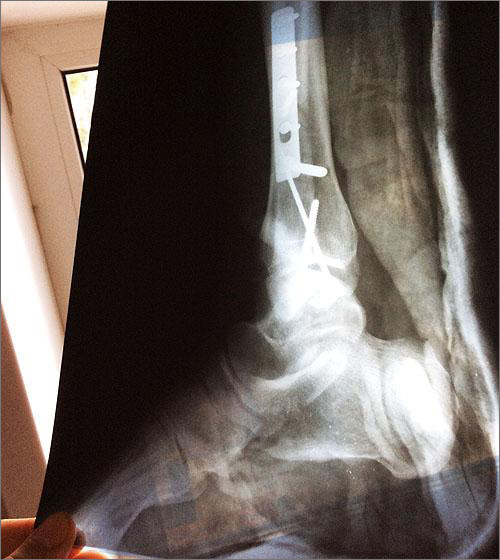

Как не пытался Владимир уйти от столкновения, но избежать удара не удалось, хотя и скорость была не высокой – 60 км/ч. В результате, журналист получил тяжелейшие травмы: практически лишился ступни правой ноги, повредил колено и позвоночник. Пережив две операции и полгода лежачего положения, он вот уже как 10 месяцев выпал из полноценной жизни. Далее Владимира ждет еще одна операция и длительная реабилитация. Однако оказалось, что это еще не все испытания, подготовленные для него судьбой.